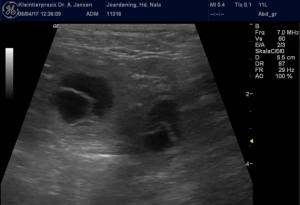

Nun begann die Tierärztin den Bauch zu schallen. Ein vorwitziger Winzling drängte sich gleich ins Bild! Sein Herz schlug deutlich und regelmäßig, sein Neuralrohr (als Vorläufer der Wirbelsäule) war noch deutlich nach innen gefaltet und offen und putzmunter schwebte er an der Nabelschnur.

Bei der weiteren Recherche bekamen wir noch die einen und die anderen ins Visier, einer hat sich ganz nah an der Blase eingenistet, das gibt später bestimmt häufige Pipi-Gänge der Schwangeren 🙂

Allen Embryos geht es gut, die Tierärztin war mit dem Gesehenen sehr zufrieden und wir natürlich auch!

Rechts könnt ihr ein Video aus den heutigen Aufnahmen sehen – wer genau hinschaut, kann die kleinen Herzen pulsieren sehen 🙂